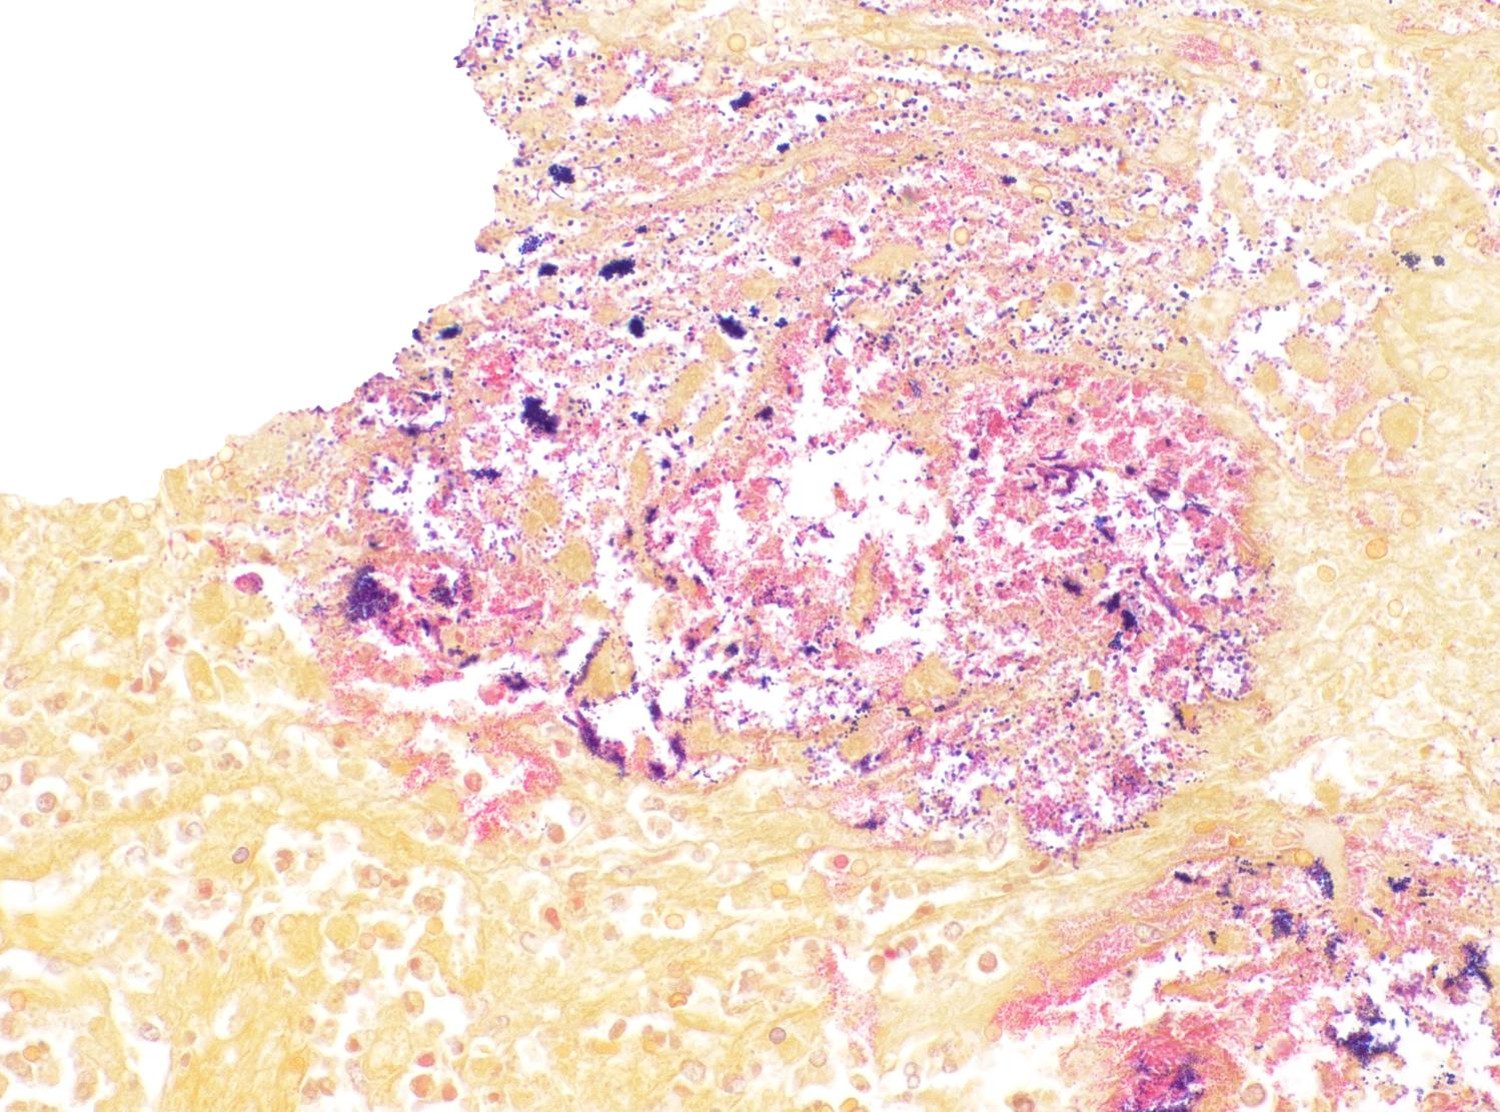

Clostridioides difficile and Salmonellatyphimurium were isolated from small intestinal and colonic content. S. typhimurium was also isolated from the liver.

In the case of S. Typhimurium, the infection was confirmed by PCR and culture followed by serotyping. Detection of this microorganism in intestinal content and liver suggests that the intestinal infection occurred before and there was systemic dissemination through the damaged intestinal mucosa, although intestinal mucosa damage is not a requirement for absorption and dissemination of this Salmonella spp.5,7

Salmonella enterica var Typhimurium, thought to be the primary pathogen in this case by both the contributor and conference participants, is a non-host-adapted species of Salmonella that causes enteric disease in numerous species.3 The overt lack of GI-associated lymphoid tissue (GALT) histologically should

clue the pathologist in to the possibility for a Salmonella infection due to its tendency to infect the GALT first. Salmonella utilizes a Type 3 secretion system (T3SS) to stimulate phagocytosis and entry into M-cells and, subsequently, macrophages in the underlying lymphoid tissue. Salmonella inhibits fusion of the phagosome and lysosome to ensure its survivability within the macrophage and begins replicating safely within a Salmonella-containing vacuole (SCV). From there, it can be trafficked throughout the body hidden within macrophages. Later, using a Type 1 secretion system (T1SS), Salmonella stimulates apoptosis of the macrophage via activation of caspase 1, enabling each Salmonella to escape the host cell and infect additional cells. In this case, Salmonella Typhimurium was cultured from the small intestine, colon, and liver, indicating a septic process.